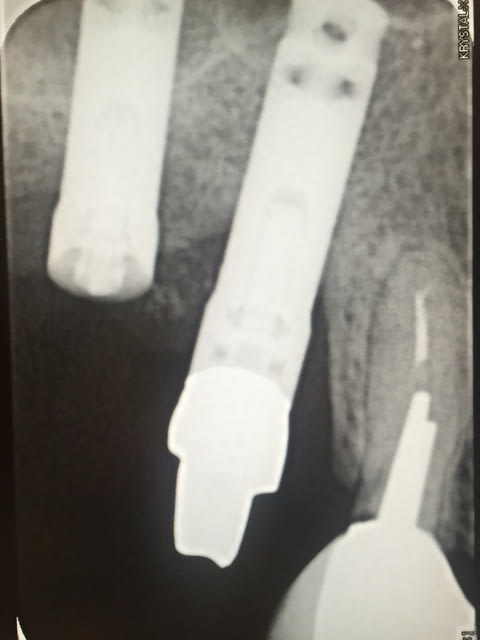

Identification Implant

Pouvez vous m'aider à identifier ces implants?

Implant impacté IMZ probablement, il sera plus facile à retirer ;)

non, c'est des press fit de chez 3M